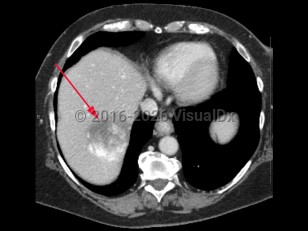

Hepatic hemangioma

Most hepatic hemangiomas are asymptomatic and are incidental findings on abdominal imaging. Larger lesions are more likely to cause symptoms, including abdominal pain (especially in the upper right quadrant), nausea, and anorexia. Women are 3 times as likely to develop hemangiomas and are more likely to experience symptoms. The etiology of hepatic hemangiomas is unclear, but hormonal influence over tumor enlargement may explain the higher incidence of symptomatic lesions in women. Lesions may grow during pregnancy and in the setting of oral contraceptive therapy. Surgical resection may be necessary for patients experiencing pain.